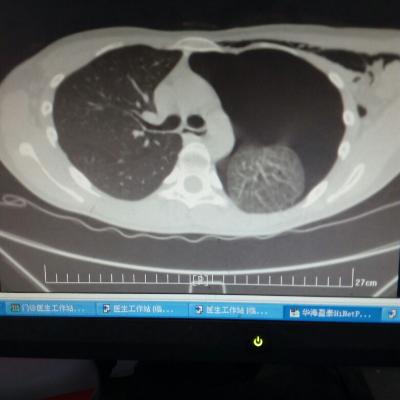

主诉:反酸、烧心5年,加重1年。 病史:患者5年前饮酒出现反酸烧心,并嗳气症状,剑突下烧灼感,饮酒及平卧后加重,无恶心呕吐,无腹痛腹泻,无吞咽困难,服用“达喜”后症状可缓解,易反复发作。3天前我科门诊示:胃镜反流性食管炎(LA-B),现为进一步诊治入院。

1.胃食管反流病 1.1反流性食管炎LA-B 2.食管裂孔疝 处理:患者诊断明确,行腹腔镜下食管裂孔疝修补术+胃底折叠术。

患者术后一周出院,反酸、烧心、嗳气症状明显缓解,无吞咽不畅等症状。 讨论:对于诊断有食管裂孔疝病人的胃食管反流病,且用药有一定疗效,建议行手术治疗,行腹腔镜下食管裂孔疝修补术,修补了膈裂孔,同时行胃底折叠术,加紧了贲门括约肌压力,共同形成抗“反流瓣”。